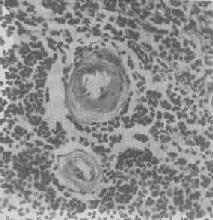

肝细胞气球样变

图1-17 肝细胞气球样变

病毒性肝炎时,肝细胞明显肿胀,胞浆疏松呈气球样

形态学:水肿的细胞体积增大,胞浆基质内水分含量增多,变得较为透明、淡染,胞核也常常被波及而增大、染色变淡、从而使整个细胞膨大如气球,故有气球变之称(图1-17)。电镜下,除可见胞浆基质疏松变淡外,尚可见线粒体肿胀及嵴变短、变少甚至消失;内质网则广泛解体、离断和发生空泡变。严重的水变性有时与渐进性坏死和坏死难以区分。